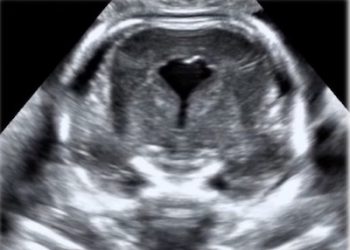

Anche a Ottobre un nuovo video "How to do"! Questo mese scopriremo come definire ecograficamente le anomalie congenite del tratto...